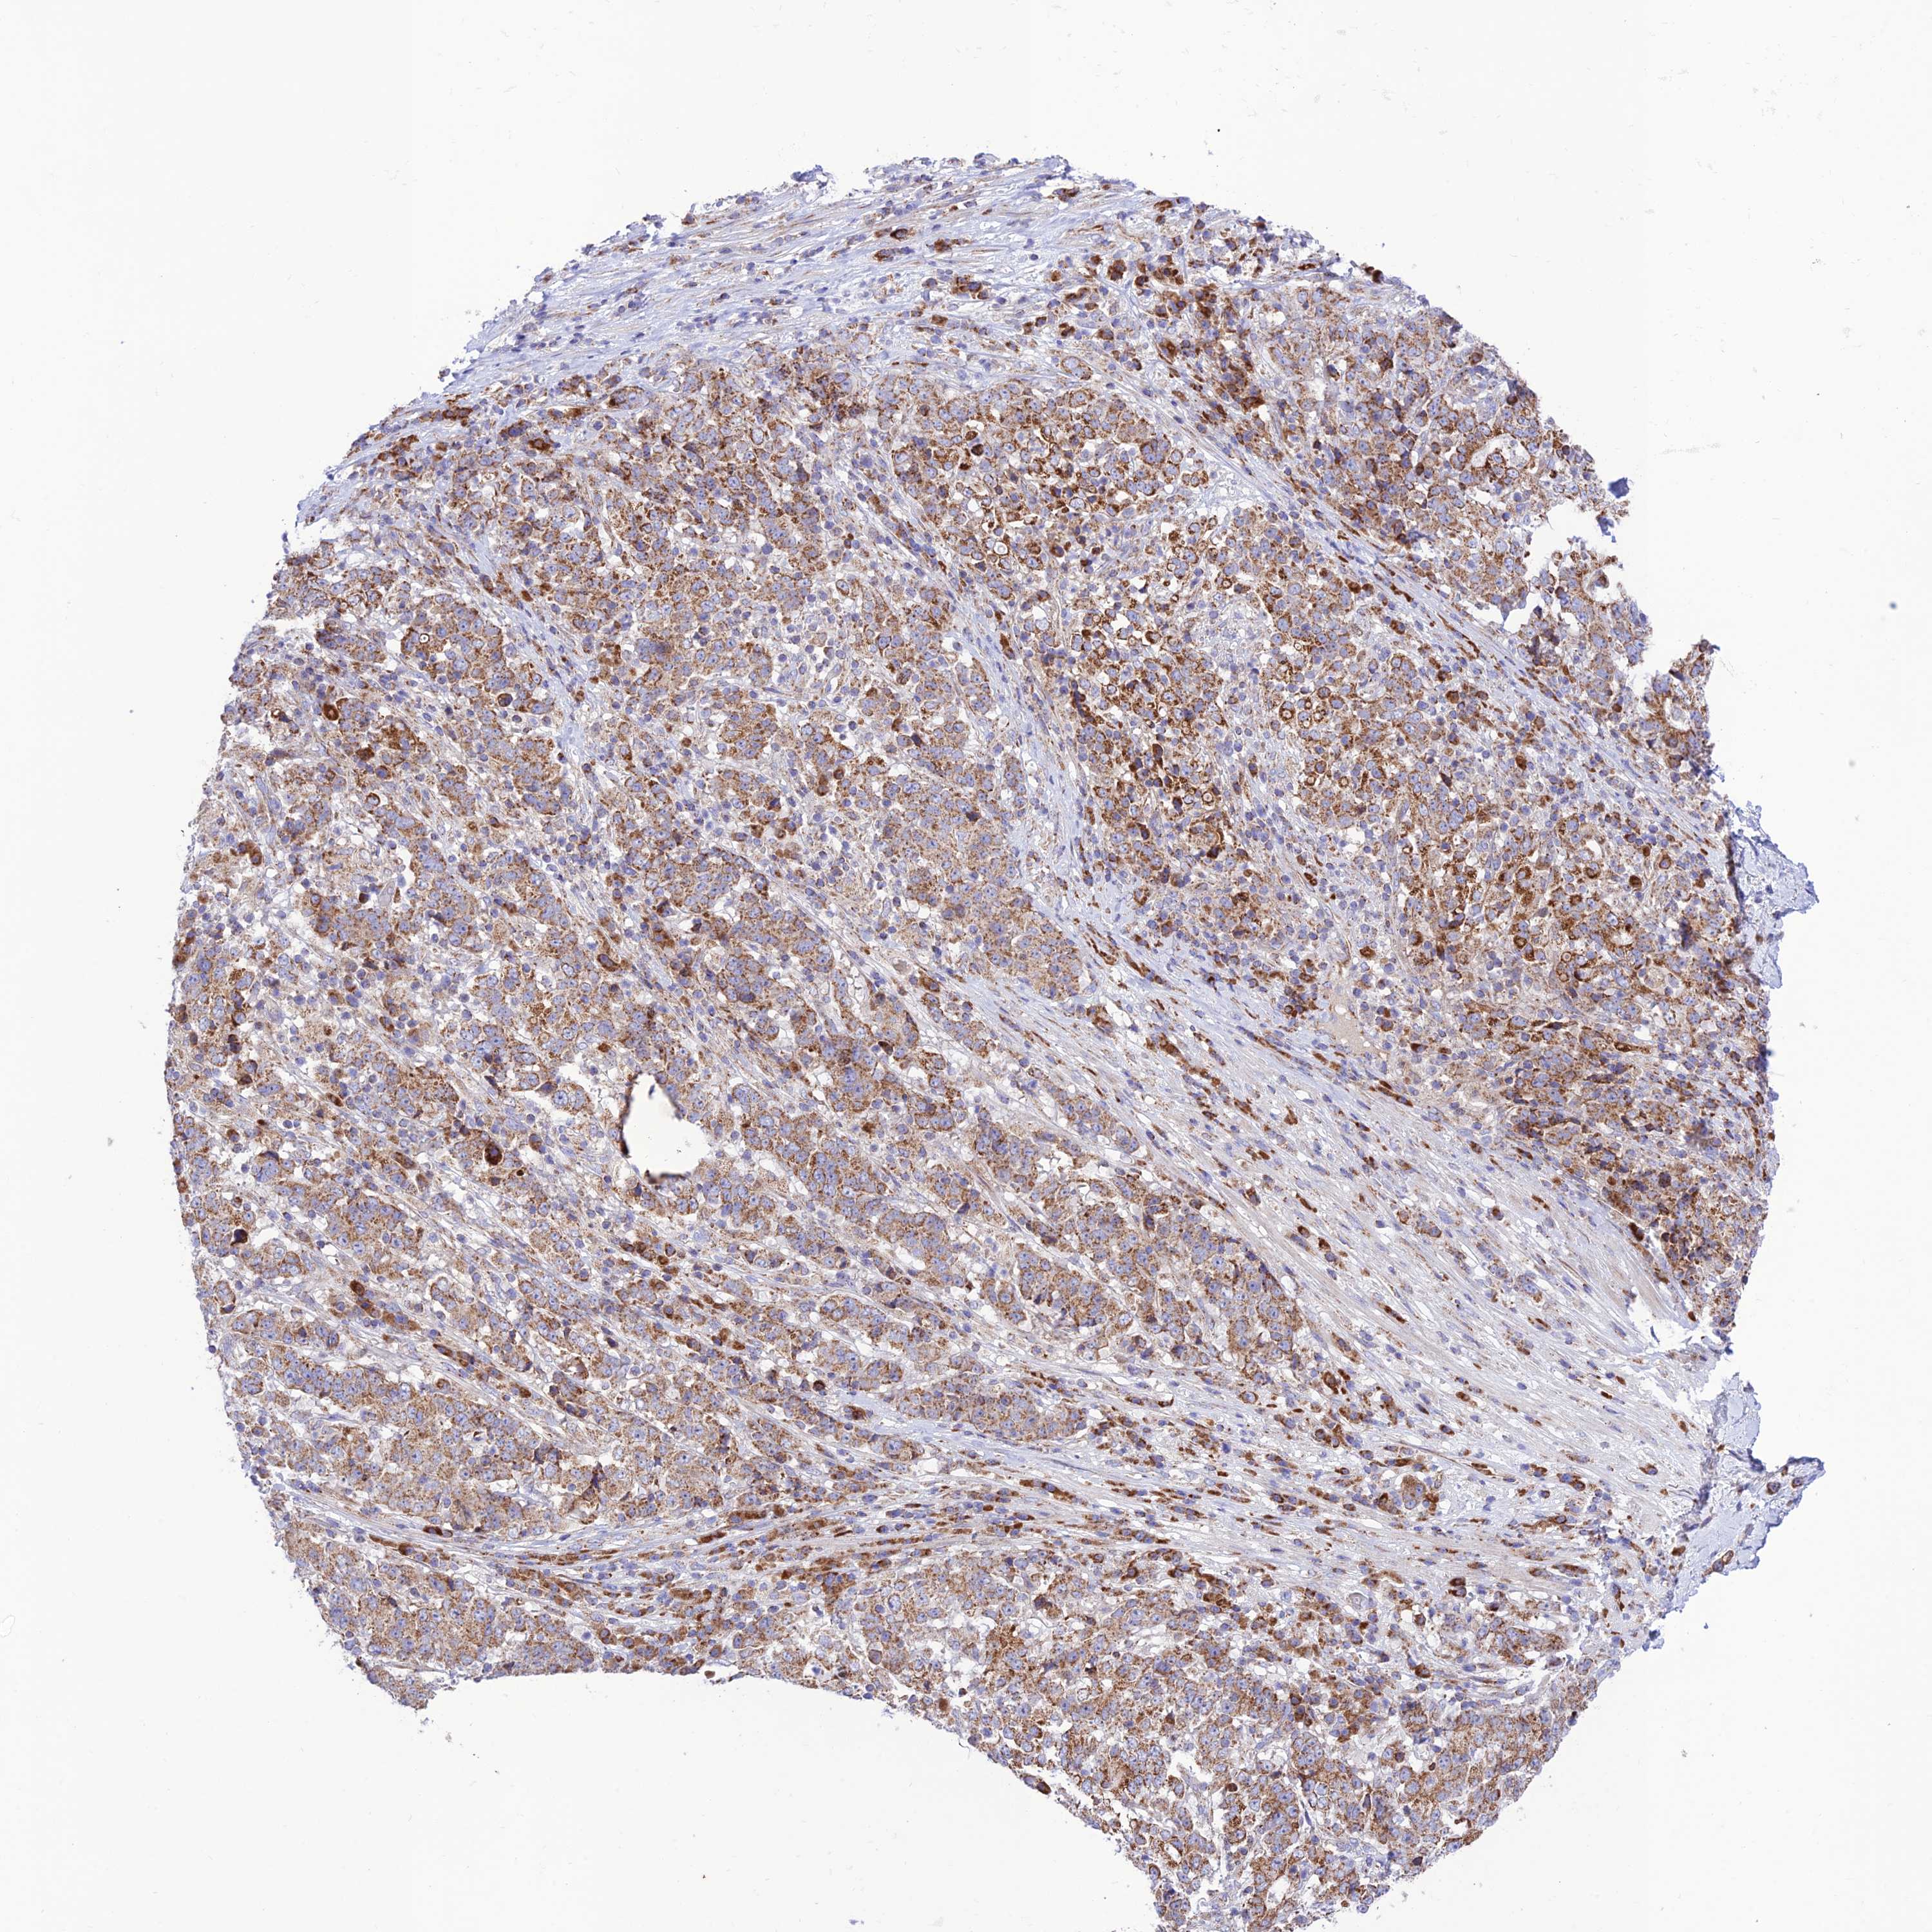

STOMACH CANCER - Protein expressioni

A mouse-over function shows sample information and annotation data. Click on an image to view it in a full screen mode. Samples can be filtered based on level of antibody staining by selecting one or several of the following categories: high, medium, low and not detected. The assay and annotation is described here.

Note that samples used for immunohistochemistry by the Human Protein Atlas do not correspond to samples in the TCGA dataset.

Antibody stainingi

Antibody staining in the annotated cell types in the current human tissue is reported as not detected, low, medium, or high, based on conventional immunohistochemistry profiling in selected tissues. This score is based on the combination of the staining intensity and fraction of stained cells.

Each image is clickable and will lead to virtual microscopy that enables deeper exploration of all samples and also displays staining intensity scores, fraction scores and subcellular localization as well as patient and tissue information for each sample.

Antibody HPA044356

Staining

High

Medium

Low

Not detected

Intensity

Strong

Moderate

Weak

Negative

Quantity

>75%

75%-25%

<25%

None

Location

Nuclear

Cytoplasmic/membranous

Cytoplasmic/membranous,nuclear

Adenocarcinoma, NOS